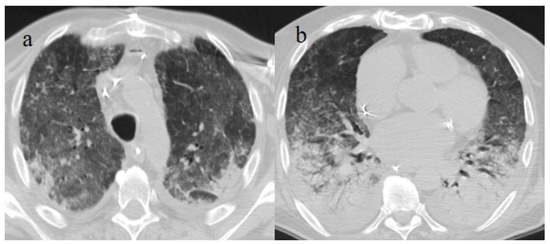

3.2. COVID-19 Pneumonia after Breakthrough Infections

- Brogna, B.; Bignardi, E.; Brogna, C.; Capasso, C.; Gagliardi, G.; Martino, A.; Musto, L.A. COVID-19 Pneumonia in Vaccinated Population: A Six Clinical and Radiological Case Series. Medicina 2021, 57, 891. [Google Scholar] [CrossRef]

- Granata, V.; Fusco, R.; Villanacci, A.; Magliocchetti, S.; Urraro, F.; Tetaj, N.; Marchioni, L.; Albarello, F.; Campioni, P.; Cristofaro, M.; et al. Imaging Severity COVID-19 Assessment in Vaccinated and Unvaccinated Patients: Comparison of the Different Variants in a High Volume Italian Reference Center. J. Pers. Med. 2022, 12, 955. [Google Scholar] [CrossRef] [PubMed]

- Lee, J.E.; Hwang, M.; Kim, Y.-H.; Chung, M.J.; Sim, B.H.; Chae, K.J.; Yoo, J.Y.; Jeong, Y.J. Imaging and Clinical Features of COVID-19 Breakthrough Infections: A Multicenter Study. Radiology 2022, 303, 682–692. [Google Scholar] [CrossRef]

- Verma, A.; Kumar, I.; Singh, P.K.; Ansari, M.S.; Singh, H.A.; Sonkar, S.; Prakash, A.; Ojha, R.; Shukla, R.C. Initial comparative analysis of pulmonary involvement on HRCT between vaccinated and non-vaccinated subjects of COVID-19. Eur. Radiol. 2022, 32, 4275–4283. [Google Scholar] [CrossRef]